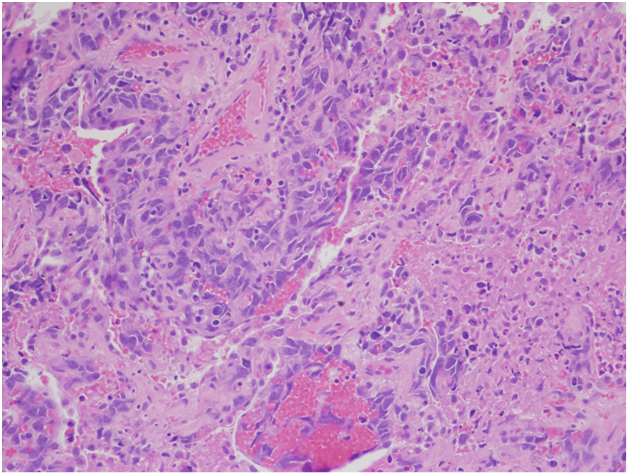

However, the wedge resection of the right lower lobe revealed angiosarcoma with lymphovascular invasion. This biopsy showed highly atypical and large malignant cells with increased mitoses (Figure 2A&2B). The immunohistochemical stains showed diffuse positivity for CD31, CD34, and vimentin (Figures 3A-3C). Stains for AE1/AE3 (Figure 3D), cam5.2, TTF-1, desmin, and OCT3/4 were negative. Along with the clinical history, a final diagnosis of angiosarcoma of the heart with metastases to the lungs was made.

The histology of this tumor has been described as irregular, anastomosing, vascular structures composed of endothelial-like cells, which can be either spindle-shaped or rounded and polygonal. Low grade lesions are composed of single- or multiple-layered vascular spaces while high grade lesions show sheets of poorly differentiated, pleomorphic cells.2 Immunohistochemical stain for CD31 is positive in 90% of PCAs and stain for FLI-1 in 100% of PCAs. Other commonly used positive stains include CD34, cytokeratins, vimentin and Factor VIII-related antigen,12 ranging from 35% to 74% positivity in PCAs described in the literature.